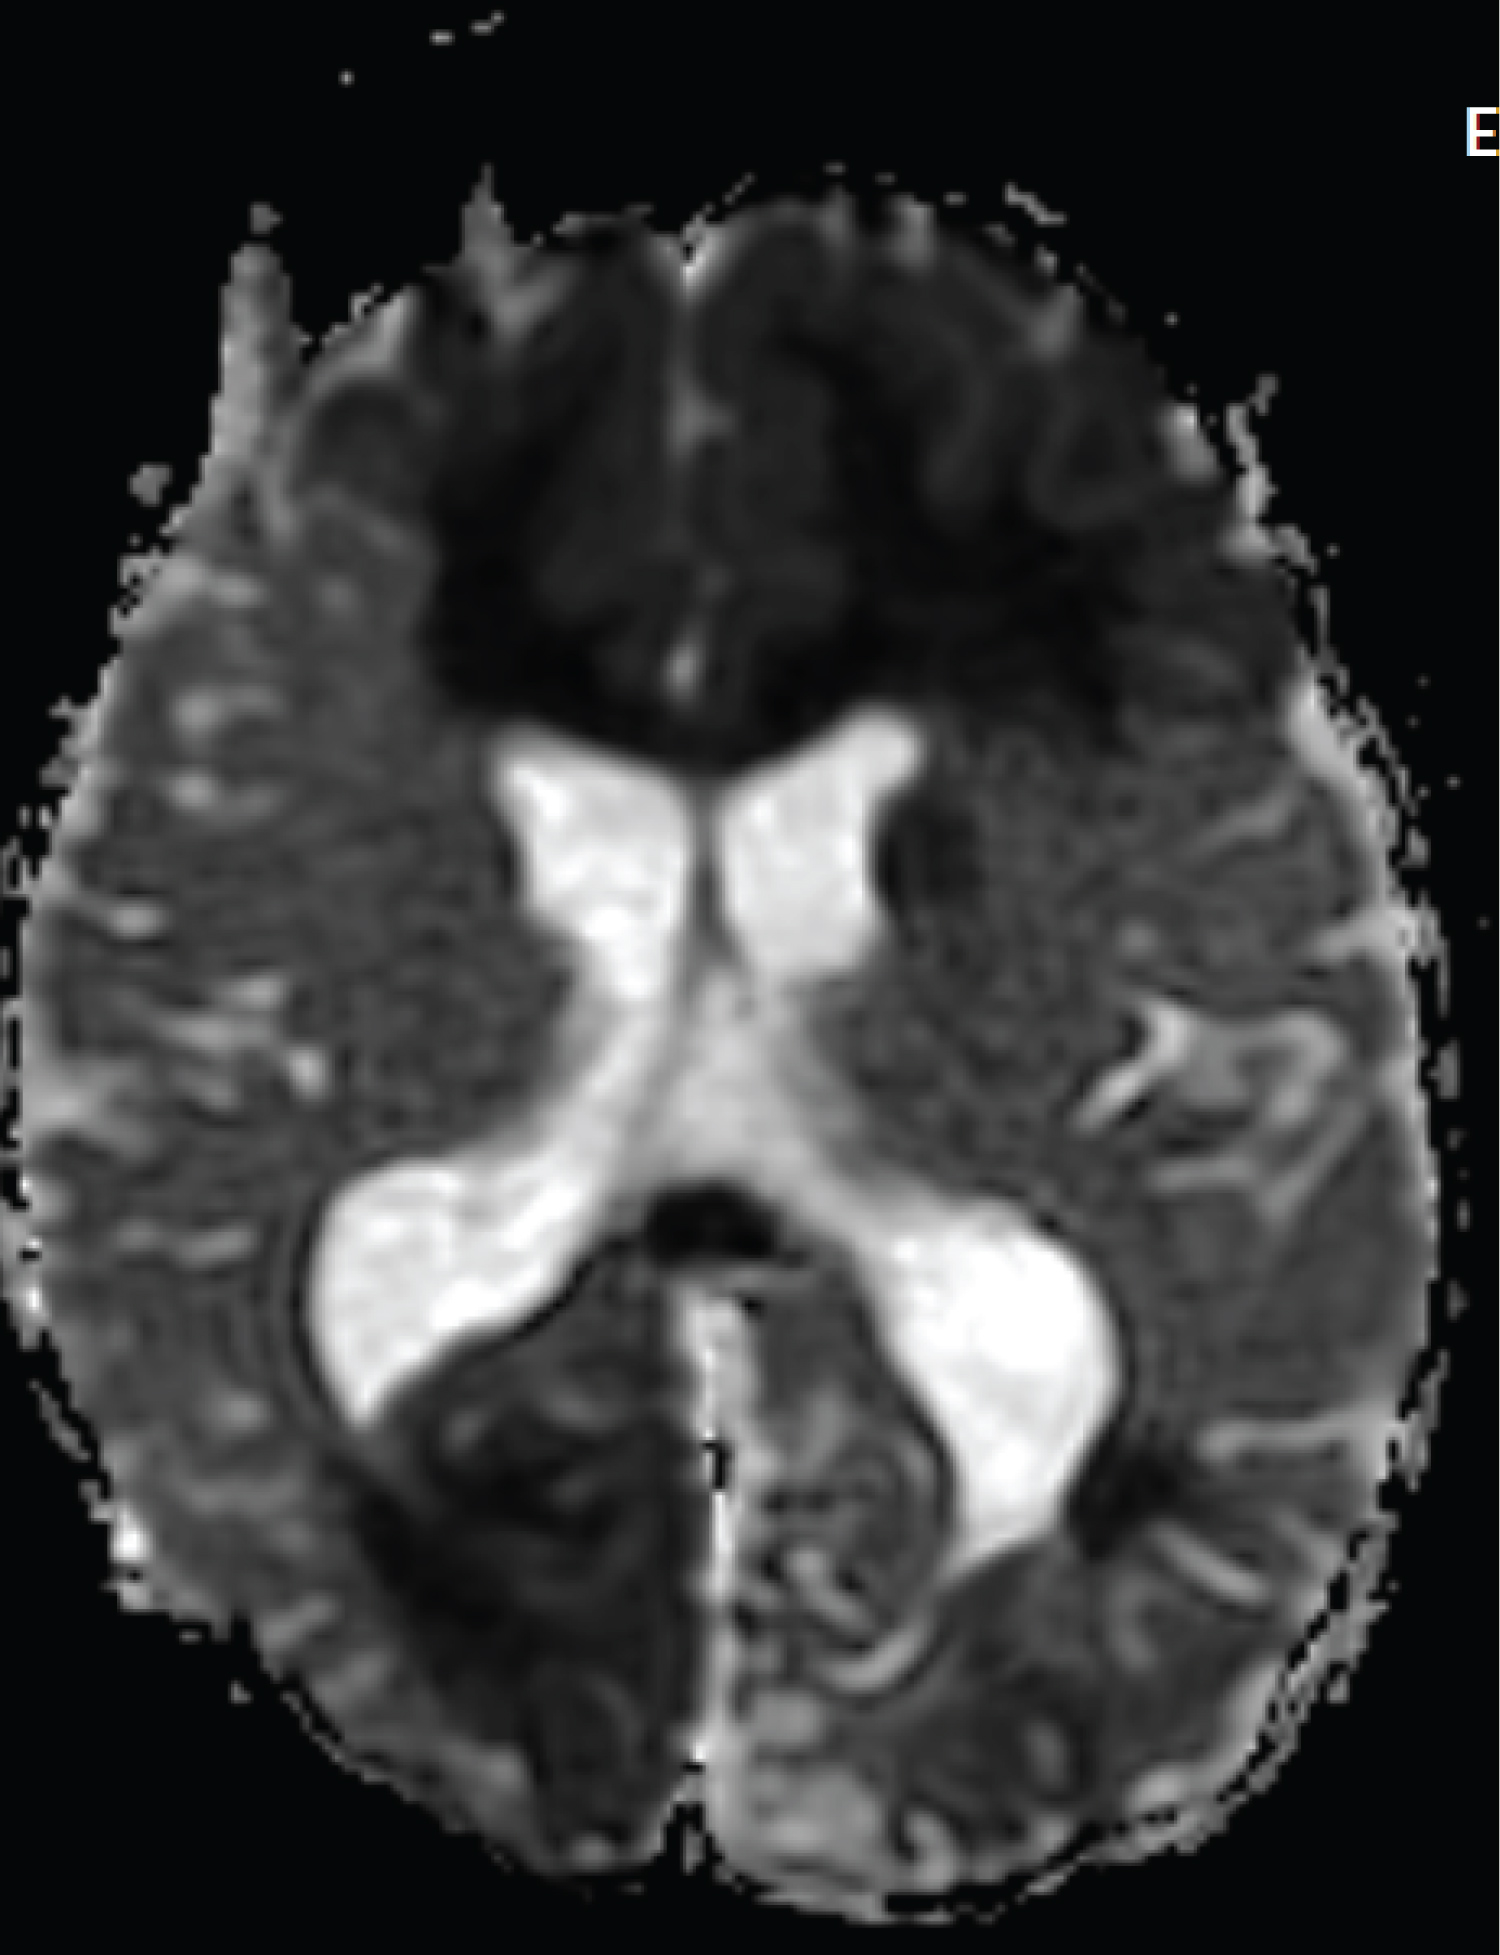

The patient is a 2-year-old child who referred to the pediatric emergency room due to loss of consciousness and suspected seizure symptoms. Also, the child's COVID-PCR test was reported positive 12 days before the visit, and the child had symptoms of cough and mild fever at the same time, which recovered at the same time. At the time of visit, the child was sleepy. He opened his eyes with painful stimulation and moved his right limbs less. Pupils were mid-sized, reactive and symmetrical. In the following examinations, there was no deviation in the eyes. Gag and corneal reflexes were normal. The child had spontaneous breathing and blood pressure and heart rate were normal. In the continuation of the history of the child, intolerance to food and milk was also mentioned. The initial blood sugar of the child was normal. After performing the initial measures, due to the unavailability of MRI, the child was subjected to brain CT scan. In the initial CT scan, the large size of the cerebral ventricles and hydrocephalus were mentioned for the child (Figure 1, Figure 2, Figure 3, Figure 4, Figure 5 and Figure 6). Due to hydrocephalus and clinical signs of increased ICP, the child was urgently transferred to the operating room, and while measuring ICP and sending a CSF sample, a ventriculoperitoneal shunt was implanted for the child. The child's icp was measured at 32 cmH2O. After the surgery, the child's level of consciousness improved relatively. The variables of the CSF sample sent were all in the normal range. The next day, the child underwent brain MRI and MRA. In the performed MRI, a clear signal change was seen in the frontal and occipital lobes, which is shown in photos No. 2, 3, 4, 5 and 6. According to the MRI, a biopsy was taken from the child's right frontal lobe for a definitive diagnosis. Immunohistochemical examination revealed the demyelinating nature of the specimen, in which extensive infiltration of basal macrophages and activated microglial cells was seen, while axons were largely preserved. No sign of vasculitis was seen in the examination of the sample. In this way, the result of the examination of the brain sample confirmed ADEM. With this diagnosis, the child was treated with corticosteroids and IVIG. The disease responded dramatically to the treatment. All the child's symptoms improved within two days and the child's level of consciousness reached its normal range. Finally, the child was discharged from the hospital after a week with a good general condition.

Figure 4: DWI image shows signal changes in the frontal and occipital lobes. View Figure 4